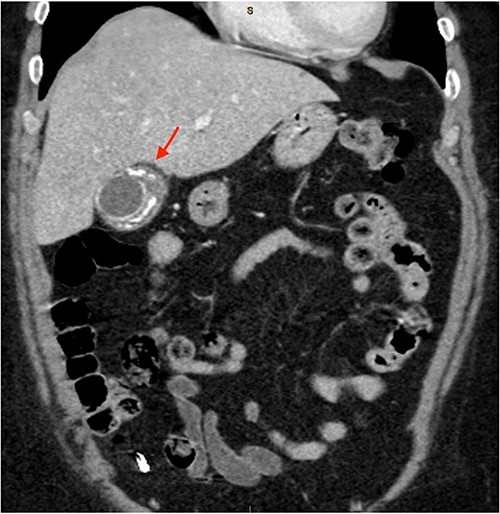

As only part of her gallbladder was imaged on the non-contrast CT lumbar spine, a repeat CT scan of her abdomen and pelvis with portal venous contrast was ordered. This showed semi-annular wall calcification at the gallbladder body suggestive for porcelain gallbladder and several calcified gallstones with largest measuring up to 32 mm (Figs 1–3). No gallbladder soft tissue mass was seen.

Semi-annular wall calcification at the gallbladder body—coronal view.